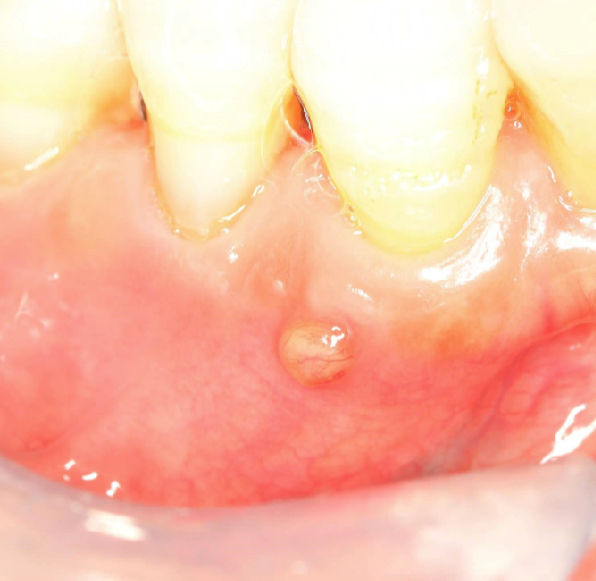

5 potential pathologies as a result of periapical inflammation

parulis: “gum boil”

3 clinical signs of parulis

dome-shaped yellow-pink papule

may/may not exhibit active suppuration (pus formation)

parulis is usually located where

on gingiva facial to non-vital tooth